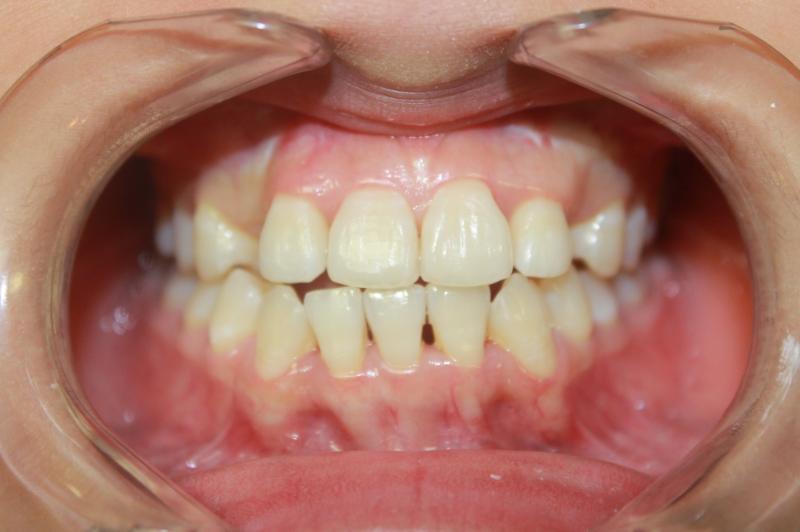

INVISALIGN - 13 months, 1 lower tooth removal, 1 series of aligners to align teeth and create the proper amount of space for 2 cantilever bridge to replace congenitally missing cuspids. COSMETIC DENTISTRY - 2 porcelain cantilever bridges and cosmetic bonding to reshape incisors and close gingival spaces. TOTAL TREATMENT TIME, 15 months

Cosmetic Dentistry, Mid-line Asymetry, Missing Teeth, Severe Crowding